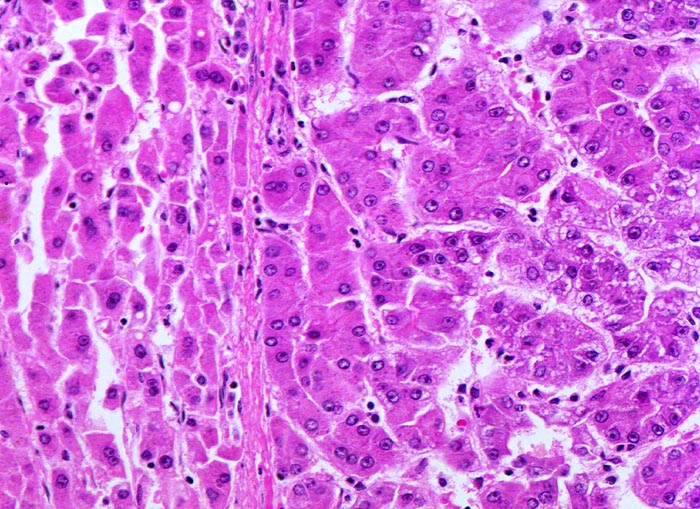

Makroskopisch imponiert das hepatozelluläre Karzinom als solitäre grosse Tumormasse, als zahlreiche zirrhoseartige Knoten oder als scharf begrenzter Knoten mit oder ohne Kapsel. Die tumorfreie Leber ist in der Mehrheit der Fälle zirrhotisch umgebaut. Mikroskopisch bilden die Tumorzellen mehr als 2 Zellen breite Trabekel (> 1237), kompakte Tumormassen (> 1229) oder pseudoglanduläre Strukturen (dilatierte Canaliculi) (> 1212) (> 1199). Desmoplastisches Bindegewebe fehlt meist. Innerhalb des Tumors fehlen Portalfelder. Es finden sich lediglich Arterien. Etwa bei der Hälfte der Karzinome lässt sich intrazytoplasmatische oder intracanaliculäre Galle (> 1238) nachweisen. Immunhistochemisch lassen sich mit einem polyklonalen Antikörper gegen Carcinoembryonales Antigen (CEA) Gallecanaliculi zwischen den Tumorzellen nachweisen. Die Tumorzellen bilden keinen Schleim.

• Die Tumorzellen bilden Trabekel, welche überwiegend mehr als 2 Zellen breit sind und Pseudodrüsen.

• Sinusoidartige Blutgefässe mit Endothelauskleidung verlaufen zwischen den Trabekeln und den Pseudodrüsen.

• Die Tumorzellen erinnern an normale Hepatozyten, sind aber kleiner als die Hepatozyten und die Kern-Zytoplasmarelation ist deutlich erhöht. Das Zytoplasma ist basophiler als das der angrenzenden Hepatozyten.

• Galle ist sichtbar in den Pseudodrüsen.